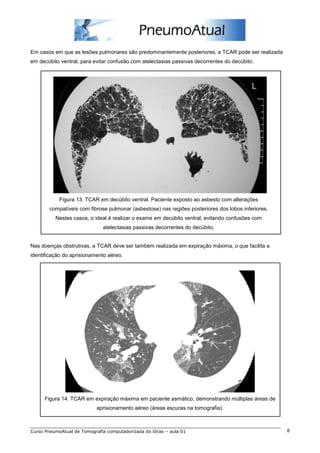

Em casos em que as lesões pulmonares são predominantemente posteriores, a TCAR pode ser realizada

em decúbito ventral, para evitar confusão com atelectasias passivas decorrentes do decúbito.

Figura 13. TCAR em decúbito ventral. Paciente exposto ao asbesto com alterações

compatíveis com fibrose pulmonar (asbestose) nas regiões posteriores dos lobos inferiores.

Nestes casos, o ideal é realizar o exame em decúbito ventral, evitando confusões com

atelectasias passivas decorrentes do decúbito.

Nas doenças obstrutivas, a TCAR deve ser também realizada em expiração máxima, o que facilita a

identificação do aprisionamento aéreo.

Figura 14. TCAR em expiração máxima em paciente asmático, demonstrando múltiplas áreas de

aprisionamento aéreo (áreas escuras na tomografia).

Em casos emque as lesões pulmonares são predominantemente posteriores, a TCAR pode ser realizada em decúbito ventral, para evitar confusão com atelectasias passivas decorrentes do decúbito. Figura 13. TCAR em decúbito ventral. Paciente exposto ao asbesto com alterações compatíveis com fibrose pulmonar (asbestose) nas regiões posteriores dos lobos inferiores. Nestes casos, o ideal é realizar o exame em decúbito ventral, evitando confusões com atelectasias passivas decorrentes do decúbito. Nas doenças obstrutivas, a TCAR deve ser também realizada em expiração máxima, o que facilita a identificação do aprisionamento aéreo. Figura 14. TCAR em expiração máxima em paciente asmático, demonstrando múltiplas áreas de aprisionamento aéreo (áreas escuras na tomografia). Curso PneumoAtual de Tomografia computadorizada do tórax – aula 01 8